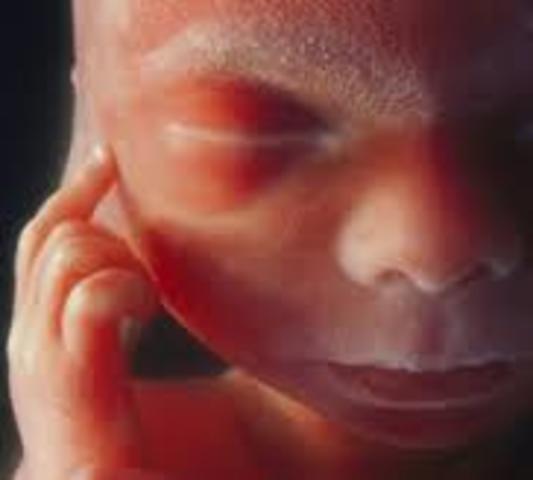

The fetus is about 6 cm long! The fetus' face is starting to form more and insulin is produced by the pancreas to help the fetus move spontaneously.